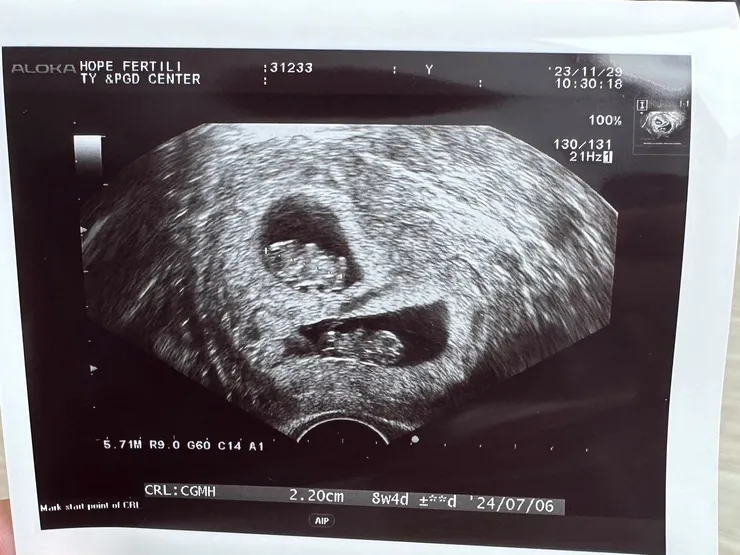

上面是B寶,下面是A寶

- A寶-8w5d、166BPM、2.28cm

- B寶-8w4d、188BPM、2.20cm

她們都有很健康的長大唷!雖然B寶的心跳有比較快(但B寶的心跳一直以來都比A寶快一點,除了落地那次的檢查兩個人的心跳差不多之外,第一次聽心跳時B寶的心跳也是比A寶快20),不過醫生說這還在可接受的範圍內,上網查了一些資訊,有些寶寶在前期懷孕的心跳就比較快,我還有看到195這種數值的!所以...應該還不需要擔心吧...(真是操碎了老父親的心呀)